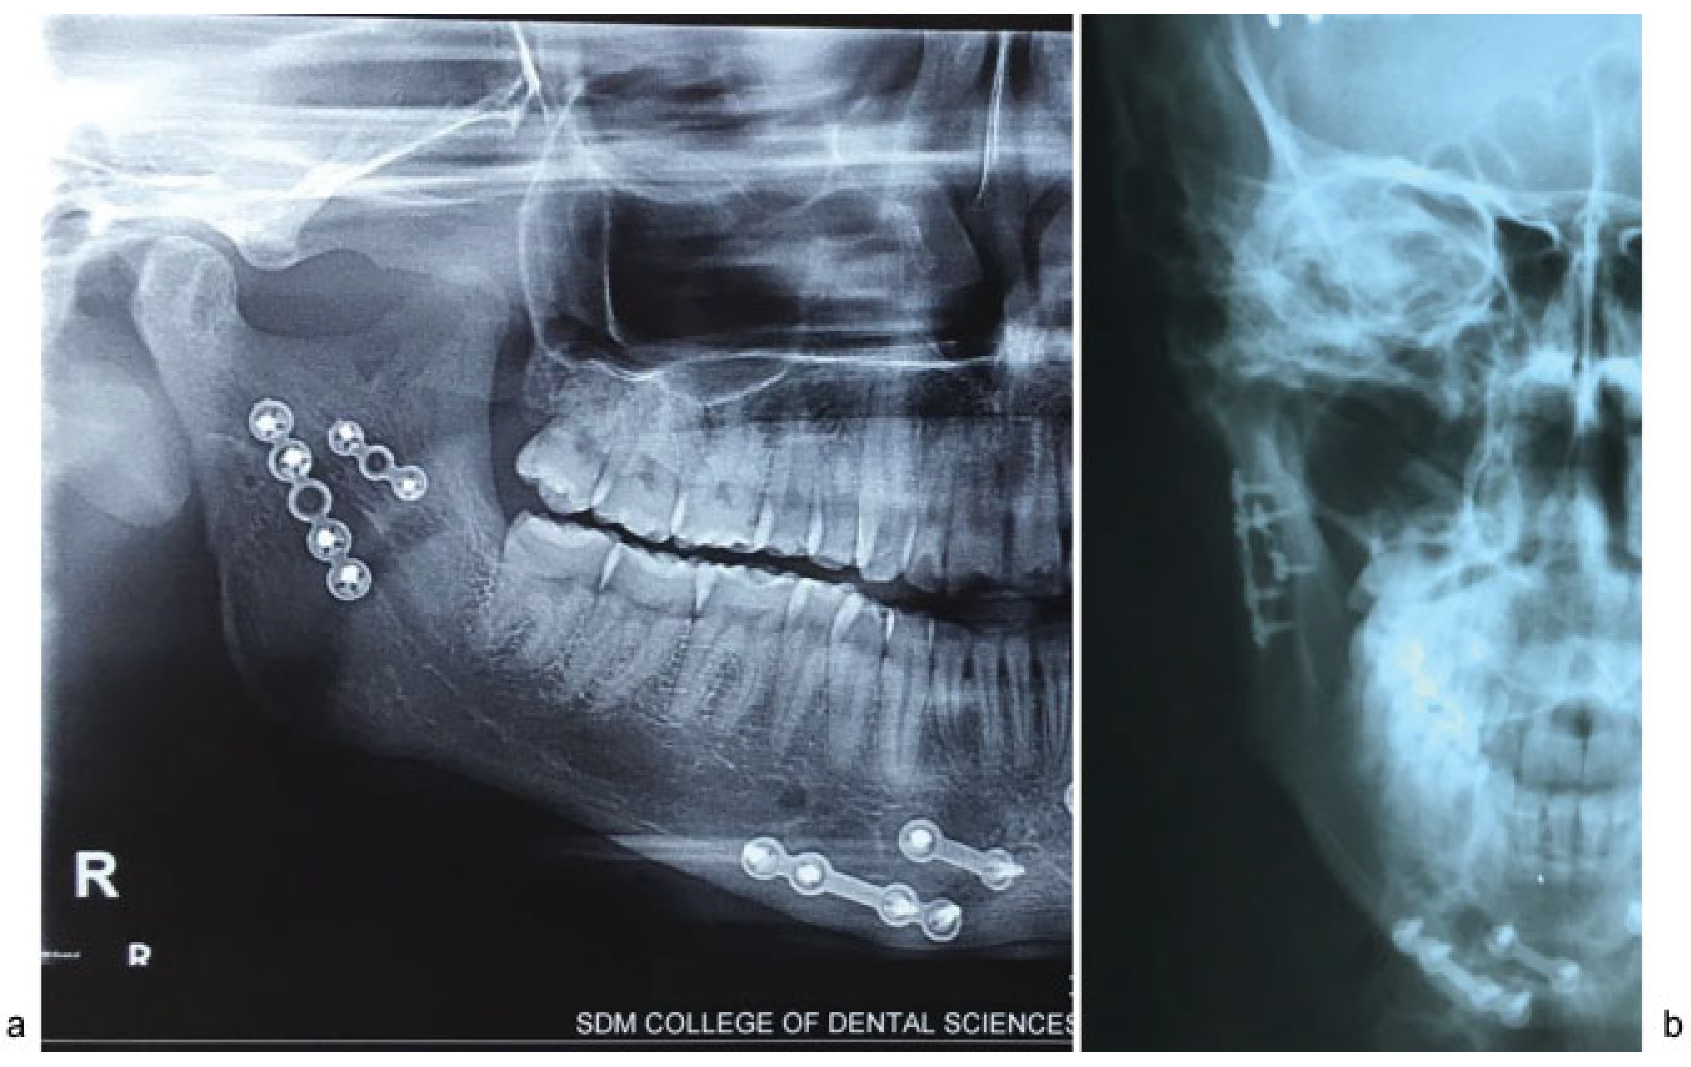

Figure 4.

(a) Endoscopic visualization of plates along the posterior aspect of lateral surface of subcondyle and another plate along the sigmoid notch. (b) Postoperative OPG shows the miniplate fixation.

Maximum intercuspation (MI) was observed in all patients except two who had occlusal interferences at the end of 1 week. Guiding elastics were continued in these two patients. Follow-ups of 6 weeks and 6 months showed MI in all patients. Deviation of jaw was assessed by residents as independent observers who were blinded about the side of surgery. Deviation of varying degrees was noted in all patients at the end of first postoperative week. At the end of 6 weeks, four patients continued to have mild deviation. One patient had deviation at the end of 6 months which was minimal compared with earlier. Facial nerve weakness was observed in one patient. One patient reported back with an extraoral draining sinus in the sixth month postoperatively. The sinus corresponded to the stab incision utilized for transbuccal fixation. The plate and screws were removed subsequently and the sinus tract excised. Generally, all patients were satisfied with the treatment at the end of 6 weeks (Figure 6).

Figure 6.

(a) Two-year postoperative OPG showing restoration of posterior ramal height and healed fracture. (b) PA mandible shows restoration of mediolateral position of proximal segment.